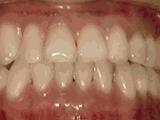

第十种:

深覆盖,咬牙时,上牙差不多完全把下牙挡住了,黄飞鸿的弟子牙擦苏就是这类,经过矫正后的牙齿是这样的~